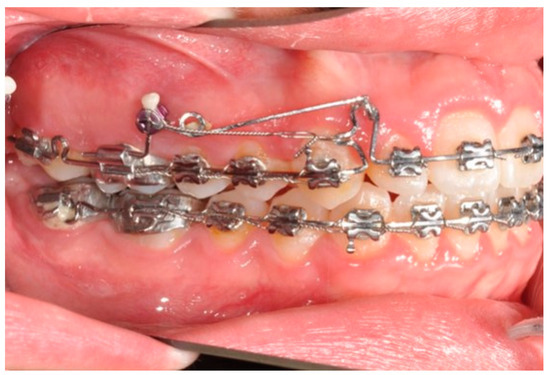

Figure 6. Molar and premolar distalization strategy: Hooks are placed between the laterals and the cuspids. Third-class elastics (1/4” 6 0z) are placed from the tads to the hooks.

After tad positioning, sequential bonding is applied on the lower arch. An 18 × 0.25 SS arch is shaped, adding a maximum 10° distal tip to the second molar. Hooks are placed between the laterals and cuspids. Third-class elastics (1/4” 6 0z) are placed from the tads to the hooks (Figure 6). The distal tip on the lower second molars will produce a gain of space between molars, with the space needed for the management of the spee curve and the recovery of IMPA.